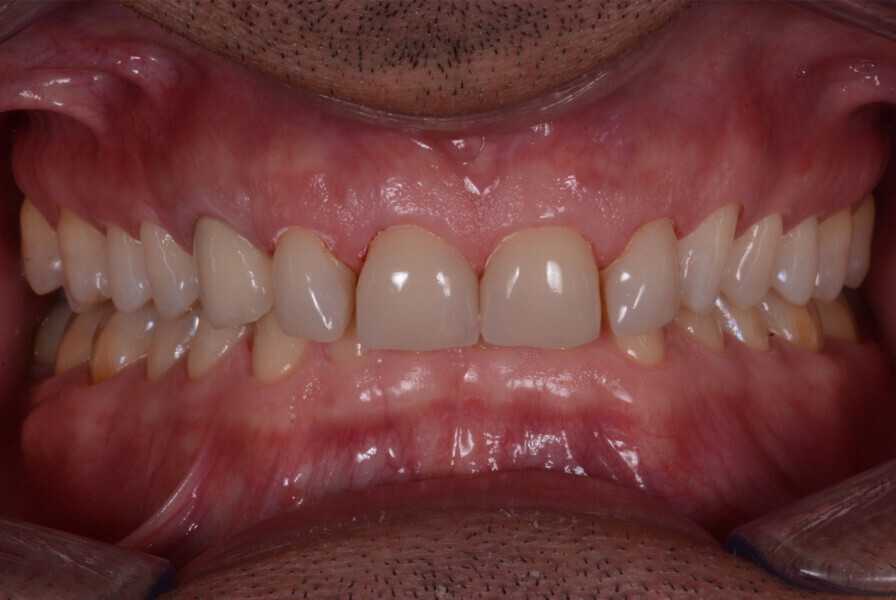

Fig. 11: The crowns (#11–13 and 21–23) and veneers (#14–17, 24–27, 31–37 and 41–47) were secured to the abutments using a light-cured resin adhesive (Futurabond U and Bifix QM).

Fig. 12: The crowns (#11–13 and 21–23) and veneers (#14–17, 24–27, 31–37 and 41–47) were secured to the abutments using a light-cured resin adhesive (Futurabond U and Bifix QM).

Fig. 13: Intraoral photographs after treatment.

Figs 14: Intraoral photographs after treatment.